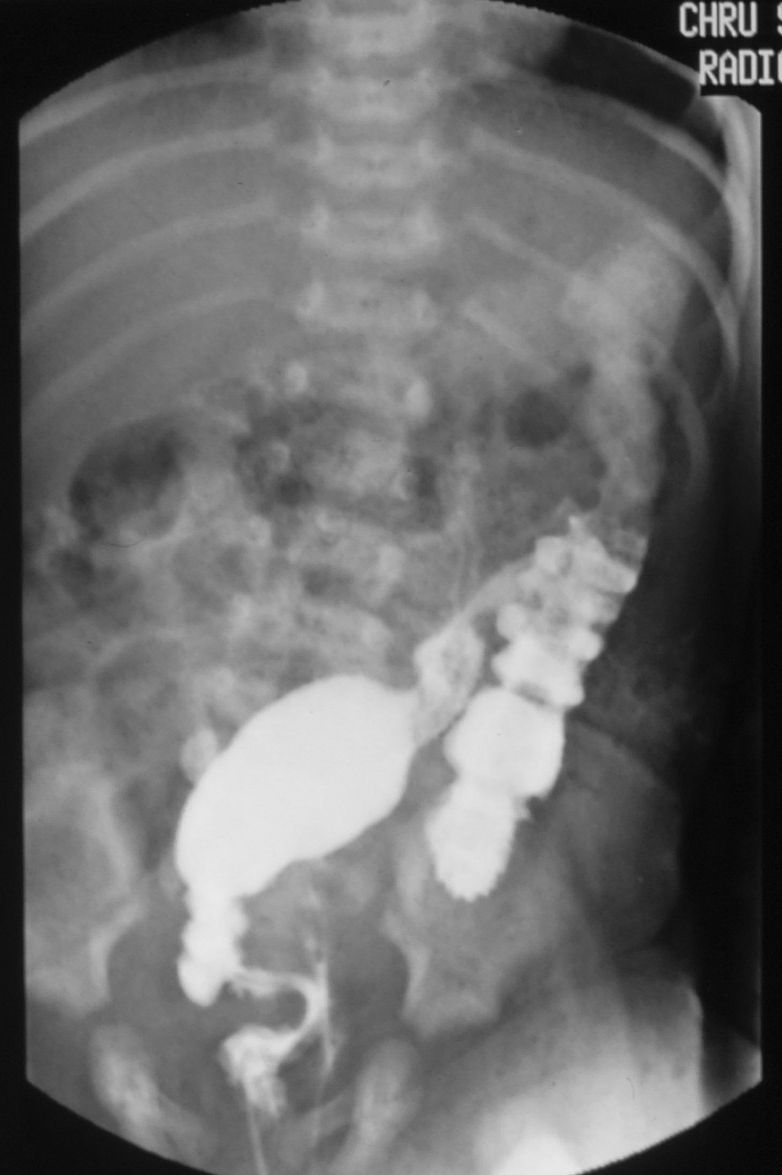

Πυλωρός είναι το τμήμα του στομάχου μεταξύ του άντρου και του δωδεκαδακτύλου. Η πυλωρική στένωση οφείλεται σε υπερτροφία του ορογόνου και του μυϊκού χιτώνα του πυλωρού και προκαλεί δυσχέρεια στην δίοδο των τροφών από τον στόμαχο στο δωδεκαδάκτυλο.

Πυλωρική Στένωση